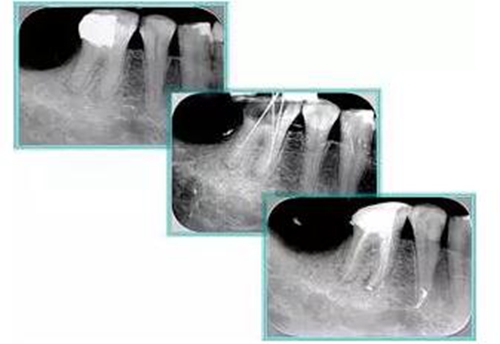

6. 術(shù)后 X 線片

術(shù)后 X 線片用來評(píng)定根管充填 長(zhǎng)度、致密度(管壁清晰、側(cè)枝)等指標(biāo)。

15.jpg

左圖為根管充填術(shù)后 X 線片。圖中可見,根管充填較好。右下圖有白色小點(diǎn),為側(cè)方加壓導(dǎo)致糊劑擠出所致,表明根管充填比較致密。

致密、恰到好處的充填可去除干凈根管里感染灶,機(jī)體逐漸恢復(fù)。

16.jpg

多根牙時(shí)候需進(jìn)行偏移投照,正位投照無法說明具體哪根牙根管充填效果。